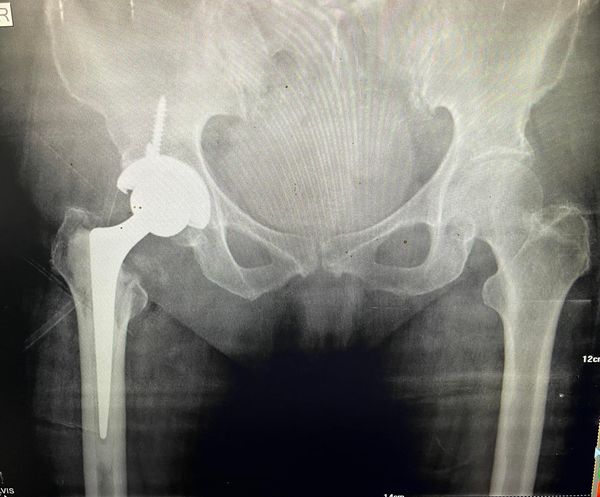

There is usually a spirited disagreement in the orthopaedic community on how to manage a neck of femur fracture like this in elderly. This is 71 year old lady with active lifestyle, who I chose to treat with total hip replacement, doing a thr arguably gives the joint a longer trouble free lifespan when compared to hemi arthroplasty.